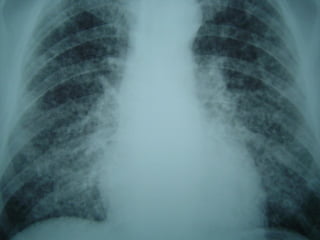

 RADIOLOGIA - ABPARADIOLOGIA - ABPA

MICOSES PULMONARES